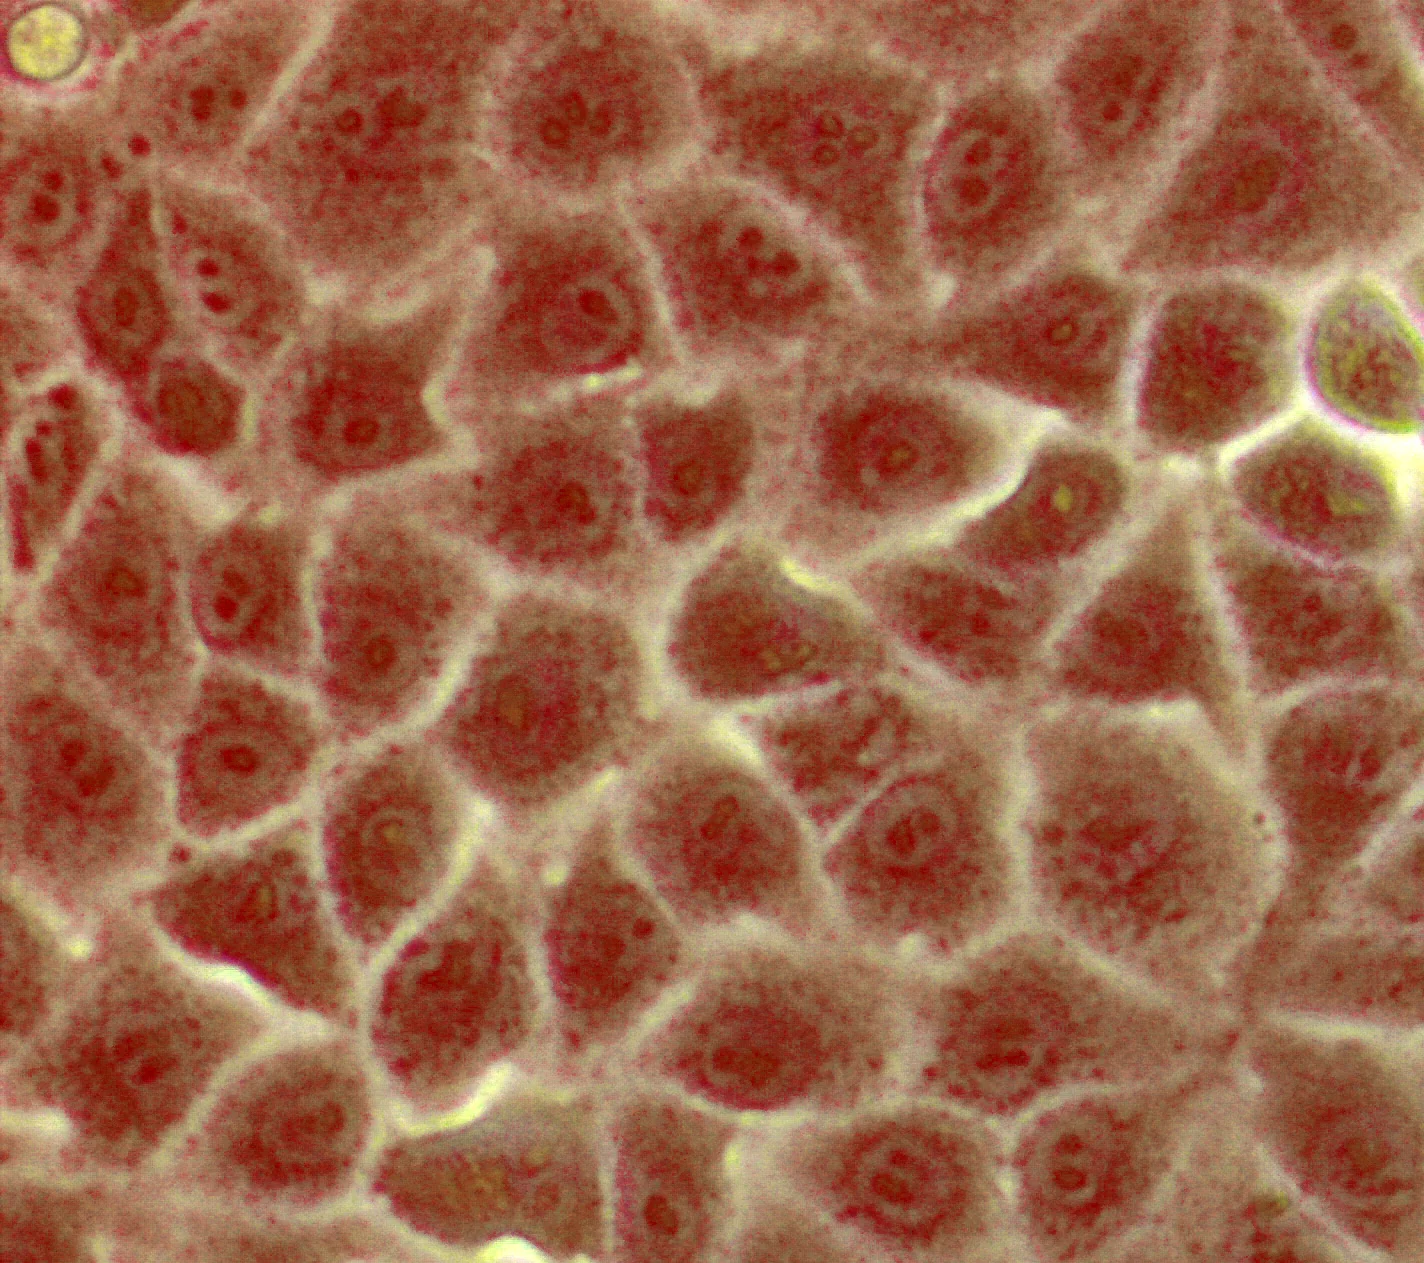

Nierenepithelzellen Zurück